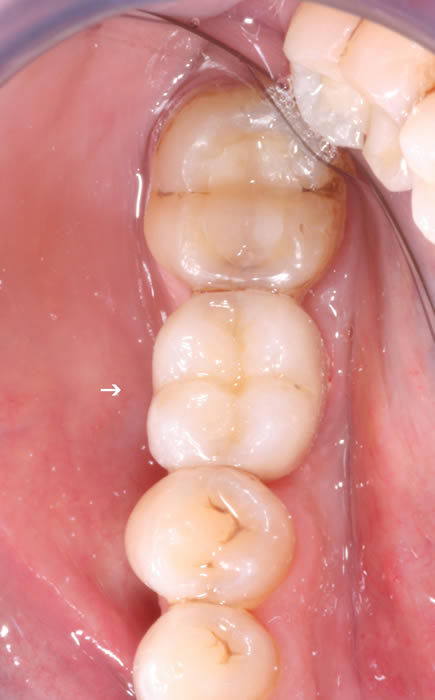

More back teeth replaced by dental implants

Case Three (2 images)

Case Four (4 images)

Case Five (4 images)

Case Six (8 images)

Case Seven (4 images)